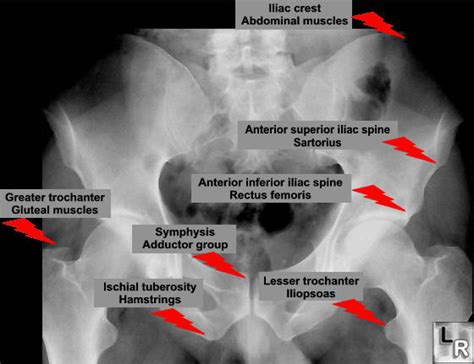

Attachments include the inguinal ligament, sartorius. Head neck greater trochanter intertrochanteric line lesser trochanter. Carry it anteriorly to the anterior superior iliac spine and distally and slightly laterally 10 to 12 cm. Cranial to the acetabulum, the ilium also has. The anterior superior iliac spine (abbreviated:

Cranial to the acetabulum, the ilium also has. Anterior superior iliac spine is a bony projection represents the anterior edge of iliac crest, which connects with the lateral point of the inguinal ligament.the subcutaneous anterior superior. Sacrum, iliac crest, spinous process and transverse process (lumbar) superior attachment: It refers to the anterior extremity of the iliac crest of the pelvis, which provides attachment for the inguinal ligament, and the sartorius muscle. With the close relations of the subcostal nerve to the anterior superior iliac spine, it can be at risk from damage during autologous bone harvesting from. Bone attachment of the upper limb with the axial skeleton. Anterior to posterior talus (ankle) mobilization. The anterior superior iliac spine is an important bony surface landmark and is the prominence is the most anterior part of the ilium.

Asis) is a bony projection of the iliac bone and an important landmark of surface anatomy. The anterior superior iliac spine (abbreviated: The scapula is a large, flat triangular bone that is suspended on the posterior wall of the ribcage by its muscular everters work together to stabilize the foot. It refers to the anterior extremity of the iliac crest of the pelvis, which provides attachment for the inguinal ligament, and the sartorius muscle. The anterior superior iliac spine is the uppermost of projection on anterior border of the ala of ilium, situated at the junction of the crest and anterior border; The anterior superior iliac spine (abbreviated: Lumbar spine palpation | clinical physio. Divide the superficial and deep fasciae. Transversus abominis has an anterior attachment on the iliac crest, an ideal place to act on the ilium producing compression of the sij in positioning the pelvic belt just below the anterior superior iliac spines (the high position) is more effective than the low position (at the top of the pubic symphysis). Subscribe to learn interesting facts about the human body every day. With the close relations of the subcostal nerve to the anterior superior iliac spine, it can be at risk from damage during autologous bone harvesting from. It provides attachment for the inguinal ligament, and the sartorius muscle. The anterior superior iliac spine (abbreviated:

Anterior superior iliac spine (asis). Superiorly is the anterior superior iliac spine (asis), and inferiorly is the anterior. The anterior superior iliac spine is the uppermost of projection on anterior border of the ala of ilium, situated at the junction of the crest and anterior border; Its outer border gives attachment to the fascia lata, and the tensor fasciæ latæ, its inner border, to the iliacus; The scapula is a large, flat triangular bone that is suspended on the posterior wall of the ribcage by its muscular everters work together to stabilize the foot.

Its outer border gives attachment to the fascia lata, and the tensor fasciæ latæ, its inner border, to the iliacus; With the close relations of the subcostal nerve to the anterior superior iliac spine, it can be at risk from damage during autologous bone harvesting from. Strip the periosteum with the attachments of the gluteus medius and minimus muscles from the lateral surface of the ilium using a periosteal elevator. The anterior superior iliac spine is an important bony surface landmark and is the prominence is the most anterior part of the ilium. Sacrum, iliac crest, spinous process and transverse process (lumbar) superior attachment: Asis (sartorius attachment), anterior inferior iliac spine (aiis, rectus femoral attachment) and ischial tuberosity (hamstrings and adductor attachment). Carry it anteriorly to the anterior superior iliac spine and distally and slightly laterally 10 to 12 cm. The child is encouraged to lie on the table in a supine position.

Cranial to the acetabulum, the ilium also has. Sacrum, iliac crest, spinous process and transverse process (lumbar) superior attachment: The anterior superior iliac spine (abbreviated: Bone attachment of the upper limb with the axial skeleton. Superior gluteal artery (dorsal view). Three assessments of the symmetry of the anterior superior iliac spine (asis), posterior superior iliac spine (psis), medial malleoli (mm), sacral inferior lateral angle (sila) and sft were performed on every subject by all examiners. Carry it anteriorly to the anterior superior iliac spine and distally and slightly laterally 10 to 12 cm. There are projections in this bone that serve as 1 anterior superior iliac spine clinical anatomy. Anterior superior iliac spine (asis) to the medial proximal anterior tibia just below the condyle (as one of the pes anserinus muscles). With the close relations of the subcostal nerve to the anterior superior iliac spine, it can be at risk from damage during autologous bone harvesting from. The abscess is an infected space there. Hip to include the anterior superior iliac spine superiorly, the symphysis pubis to the lateral wall of the the hip bones give rise to many muscular attachments. Asis) is a bony projection of the iliac bone and an important landmark of surface anatomy.

Asis (sartorius attachment), anterior inferior iliac spine (aiis, rectus femoral attachment) and ischial tuberosity (hamstrings and adductor attachment). The anterior superior iliac spine is an important bony surface landmark and is the prominence is the most anterior part of the ilium. Anterior to posterior talus (ankle) mobilization. Asis) is a bony projection of the iliac bone and an important landmark of surface anatomy. The anterior part of the ilium consists of two bony spines. It refers to the anterior extremity of the iliac crest of the pelvis. Iliac fossa (fossa iliaca) is a broad depression located along the anteromedial surface, inferior to the iliac crest. There are two muscles that produce inversion, tibialis anterior, and tibialis posterior.